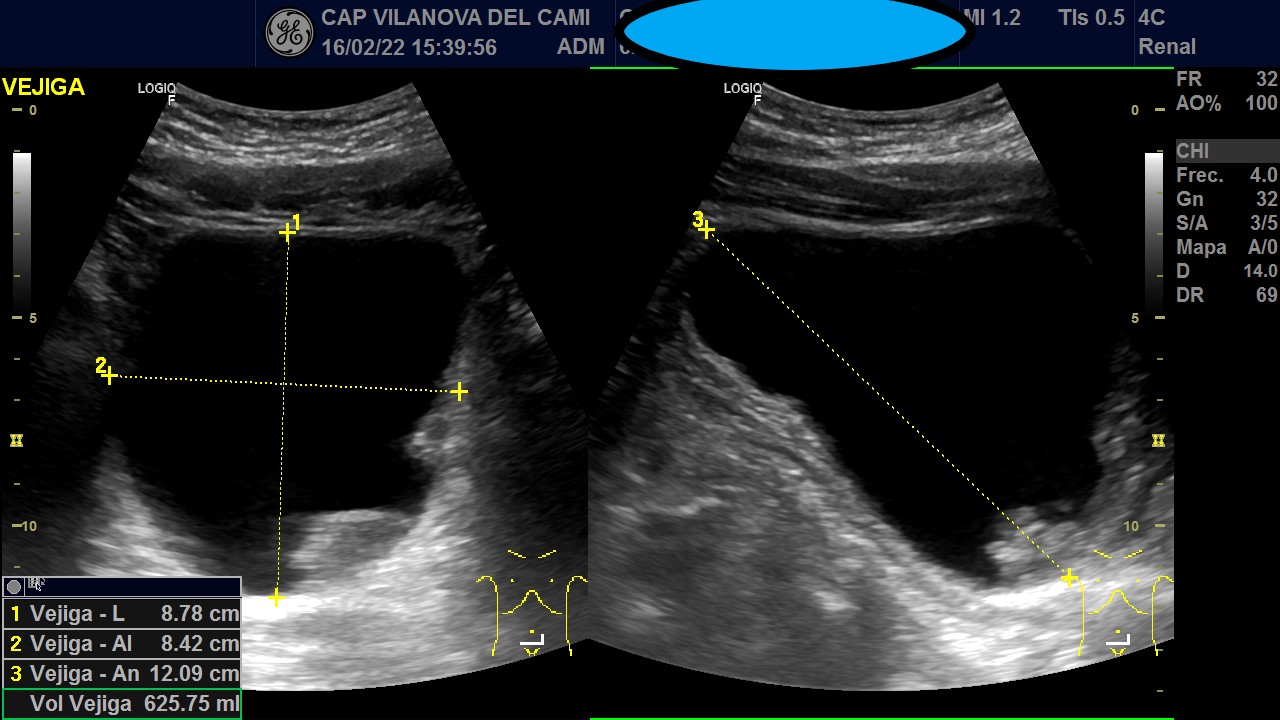

Vejiga urinaria bien distendida, de paredes engrosadas, con imágenes sugestivas de patología intraluminal y parietal. Neoformación irregular en pared posterolateral izquierda y suelo pélvico, que respeta el trígono vesical y la salida del meato ureteral, con captación Doppler color y algunas imágenes hiperecogénicas sugestivas de calcificación en su interior.